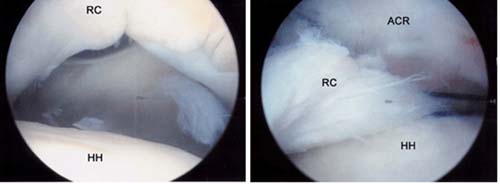

Left, Arthroscopic view of the rotator cuff from within the joint shows the rotator cuff (RC),

the head of the humerus (HH), and the biceps tendon (B).

Left, Arthroscopic view of rotator cuff tear. A large gap can be seen between the

edge of the rotator cuff and humeral head.